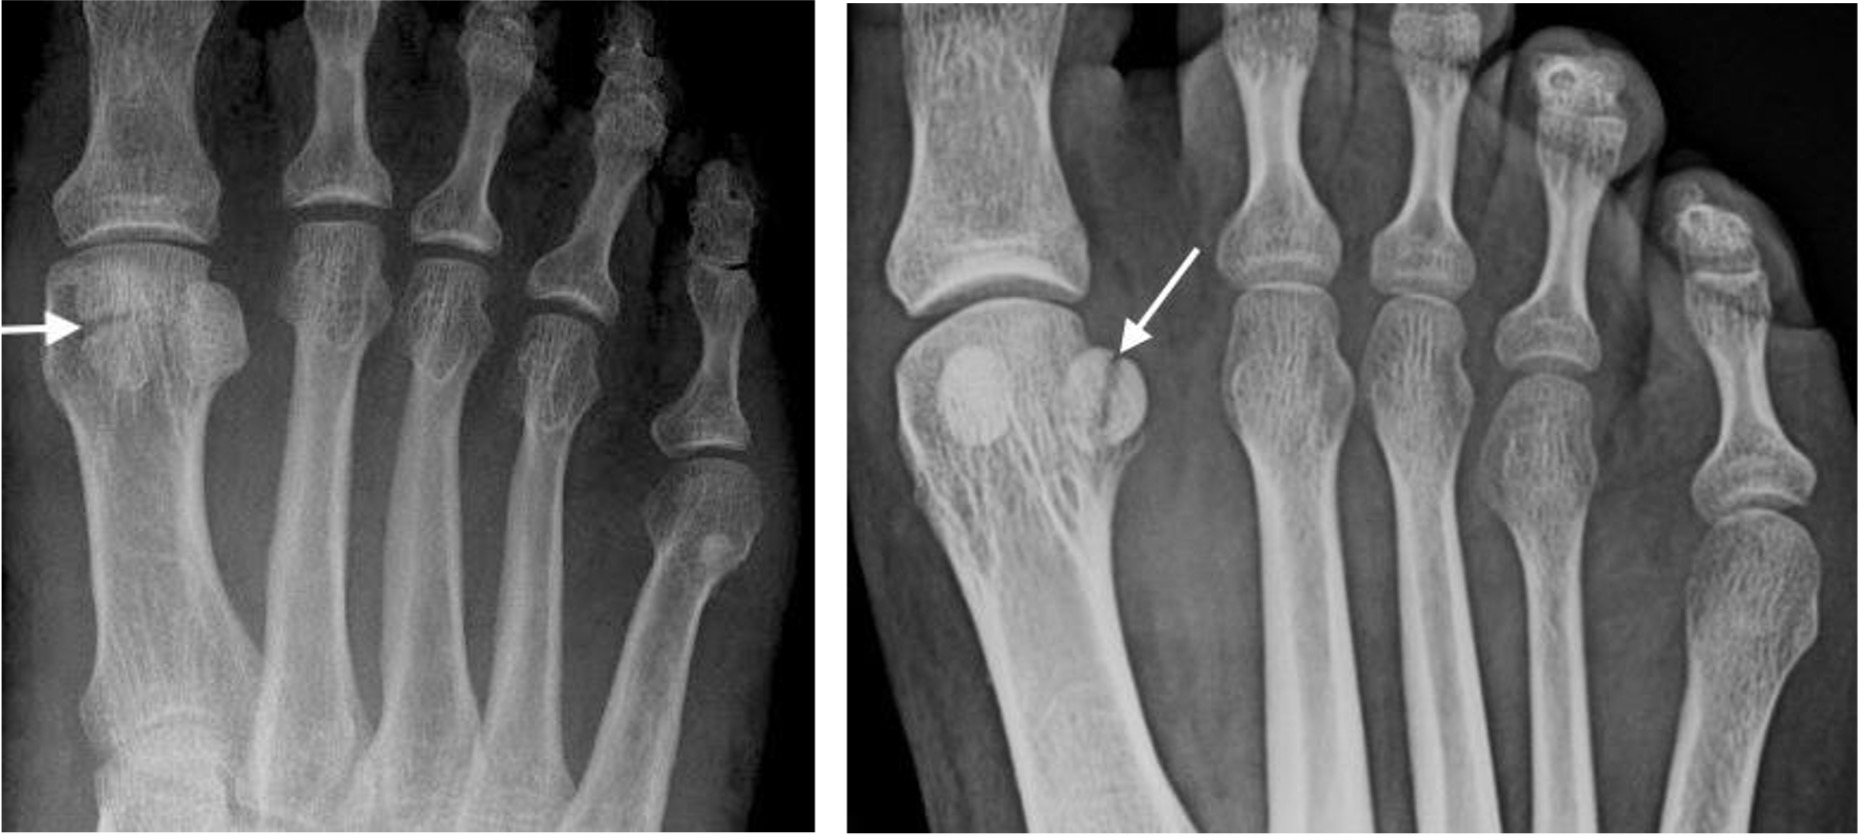

Sesamoid fracture

Commonly mistaken for a bipartite sesamoid.

Bipartite sesamoid:

Smooth, well-corticated transverse lucency with rounded margins; bipartite usually larger than single sesamoid thus the sum of the two parts is greater than the adjacent sesamoid.

Sesamoid fracture:

Painful, non-corticated fracture line separating irregular opposing sesamoid fragments with sharp edges.

Bipartite sesamoid Sesamoid fracture